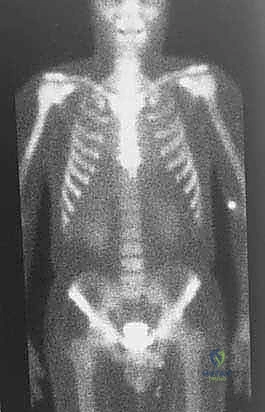

تحديد مراحل الورم (Staging): نظام Enneking

تحديد مرحلة الورم هو الخطوة الأهم قبل أي تدخل جراحي. يعتمد الدكتور هطيف على نظام (Enneking) لتحديد مراحل أورام العظام، والذي يعتمد على ثلاثة عوامل:

1. درجة الورم (Grade - G): بناءً على الفحص النسيجي (G1 منخفض الدرجة، G2 عالي الدرجة).

2. الموقع (Site - T): هل الورم داخل الحيز العظمي (Intracompartmental - T1) أم اخترق القشرة وخرج للحيز الخارجي (Extracompartmental - T2)؟

3. الانتشار (Metastasis - M): هل انتقل الورم لأعضاء أخرى (M0 لا يوجد، M1 يوجد انتشار)؟

بناءً على هذا التقييم الدقيق، يتم وضع خطة جراحية متكاملة لضمان استئصال الورم بالكامل دون ترك أي خلايا سرطانية.